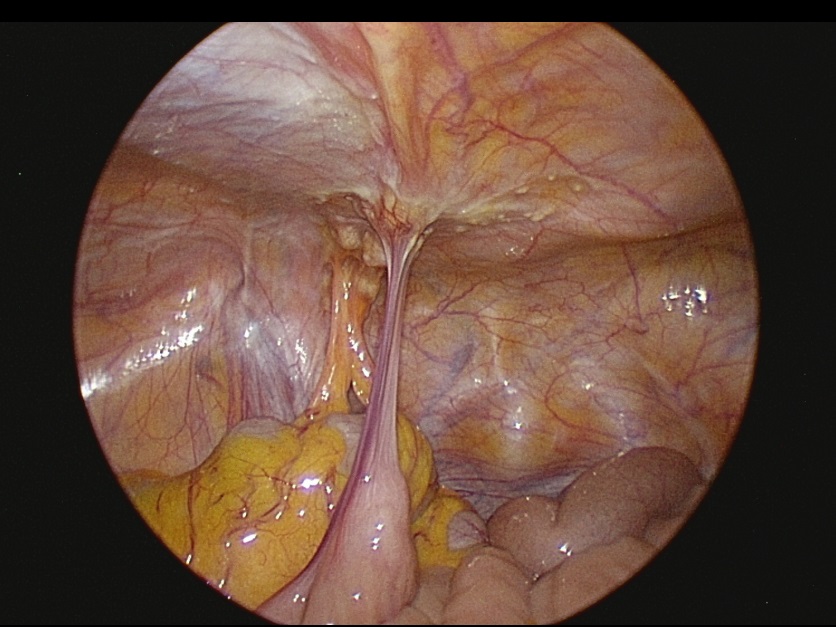

其中,「腹腔高壓氣霧化學治療(PIPAC)」為以腹腔鏡進行的微創治療方式,能在高壓環境下將化療藥物霧化,使藥物均勻分布於腹腔,為部分腹膜癌病人提供新的治療可能。臨床觀察顯示,接受PIPAC治療後,部分病人症狀與腫瘤控制情形獲得改善,有助於後續治療評估。

在風險與效益審慎衡量下,醫療團隊亦可進一步安排腫瘤減積手術(CRS),合併術中腹腔溫熱化學治療(HIPEC),清除可見病灶並降低腹腔內殘留腫瘤負荷。相關治療有助於延緩疾病進展,並提升部分病人的生活品質。